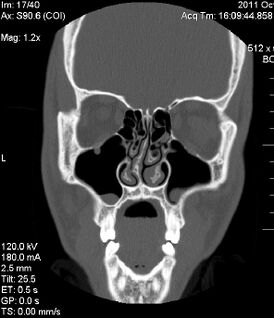

Искривление перегородки носа

Искривле́ние носово́й перегоро́дки — отклонение перегородки в обе или одну сторону от средней линии. Проявляется затруднением или отсутствием носового дыхания через один или оба носовых хода. Затрудняя отток секрета из придаточных пазух, повышает склонность к возникновению воспалительных и аллергических заболеваний органов дыхания, в том числе насморка, аллергического ринита, вазомоторного ринита, гайморита, синусита, тонзиллита.